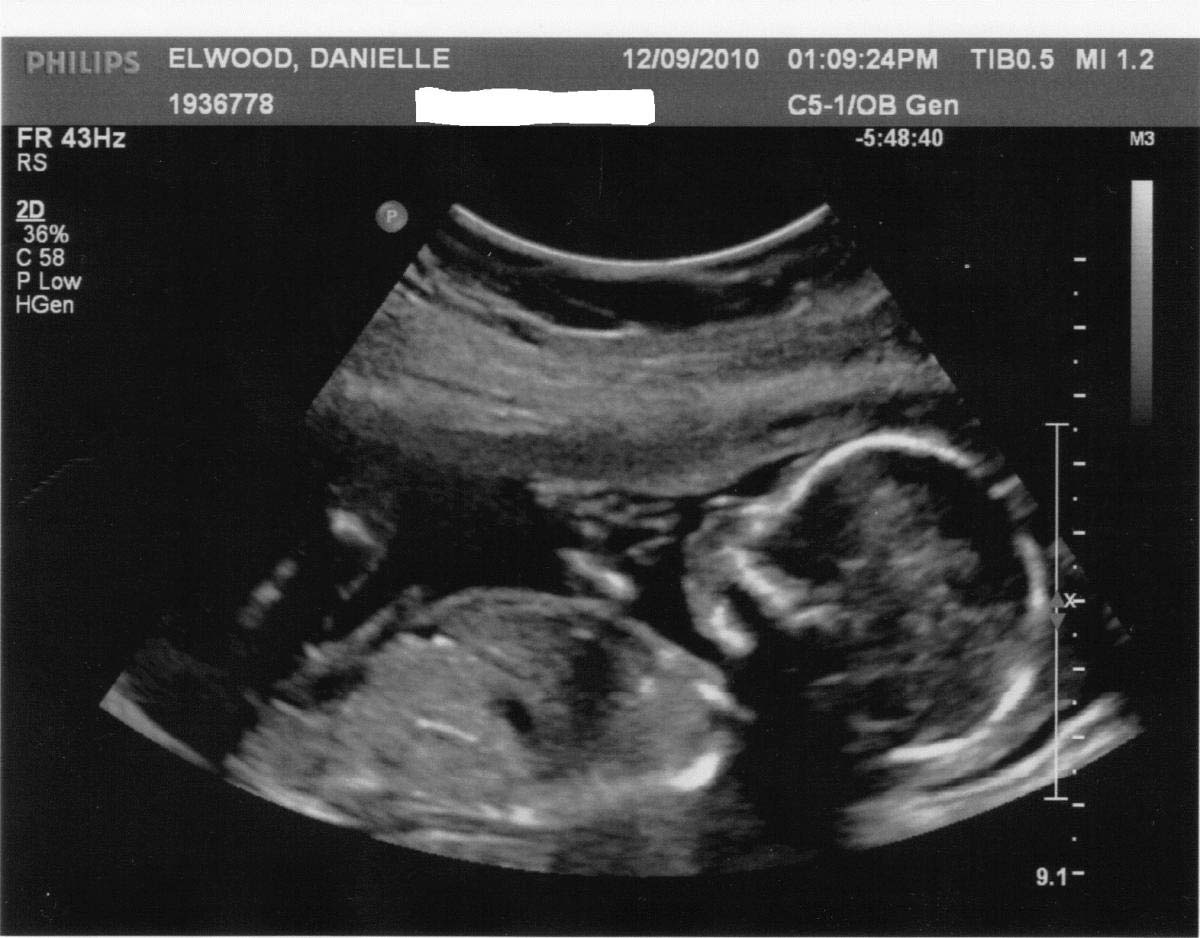

Результаты УЗИ на 29 неделе беременности, обследования и анализы

Стоит отметить, что УЗИ на 29 неделе назначают редко, ведь плановое обследование третьего триместра проходят на 30-34 неделе. И все же будущей маме его могут назначить, если недавно она перенесла инфекционное заболевание.

Одной из важнейших задач УЗИ является выяснение предлежания плода. Обычно к этой неделе он занимает правильную позицию, но может до конца держать родителей в напряжении и поменять положение только перед родами.

Проверяют во время исследования и развитие ребенка, его фетометрию: бипариетальный и лобно-затылочный размеры, окружность живота и головы, длину самых крупных костей.

Что касается организма матери, то на УЗИ врач оценивает количество и качество амниотической жидкости как один из показателей нормы развития ребенка. Ее объем может говорить о работе почек малыша, а консистенция – о возможных инфекциях.

Если УЗИ проводится на 29 неделе беременности, четко видна половая принадлежность малыша. У мальчиков на этом сроке продолжается опускание яичек в мошонку. У девочек клитор немного выдается, так как он еще не прикрыт малыми половыми губами.

Если раньше не удалось определить пол будущего ребенка, то на 29 неделе это можно узнать наверняка при помощи УЗИ. Проводя ультразвуковое исследование, оценивают не только состояние плода, но и плаценту. Ее нормальная толщина на данном этапе составляет 29 мм, а степень зрелости должна быть нулевой. Если обнаружится, что вес малыша превышает норму, беременной скорректируют рацион питания. Важным показателем является сердцебиение плода.